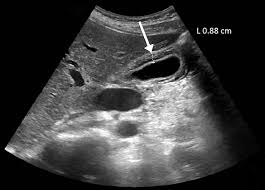

يشمل التقييم التشخيصي التصوير بالموجات فوق الصوتية والتصوير المقطعي المحوسب وتصوير الأوعية الصفراوية.

يتكون العلاج النهائي من استئصال المرارة أو أنبوب تصريف المرارة في حالة المرشحين الجراحية الضعيفة. يعد العلاج بالمنظار مع التصريف والغسيل من القنوات الصفراوية خيارًا علاجيًا فعالًا للمرضى غير القادرين على تحمل الجراحة أو فغر المرارة.